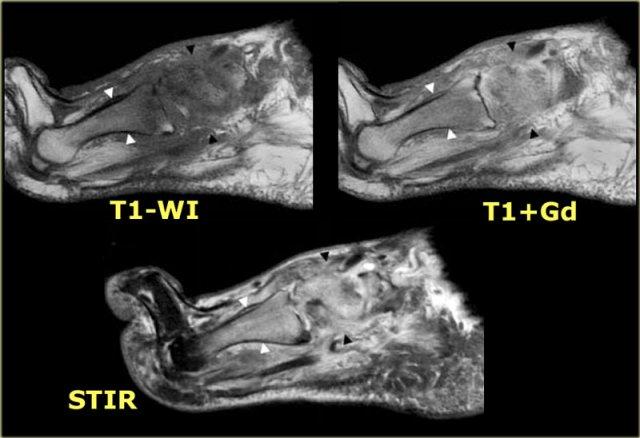

STIR and T1W images in Charcot neuro-osteoarthropathy with a plantar ulcer (asterix) and osteomyelitis of the cuboid.

Ở bệnh nhân bị bệnh khớp xương thần kinh Charcot và bàn chân đế lắc, xương hộp là vị trí quan trọng của viêm tủy xương.

Nếu hình ảnh T1 tại vị trí đó cho thấy cường độ tín hiệu thấp kết hợp với khuyết hổng da, viêm tủy xương là cực kỳ có khả năng.

Hình ảnh STIR và T1 bên trái của bệnh nhân bị bệnh xương khớp thần kinh Charcot đang hoạt động với vết loét lòng bàn chân dọc theo chỗ lồi xương của xương hộp.

Có tín hiệu bất thường trong xương hộp cạnh vết loét, gợi ý viêm tủy xương.

Đây là các hình ảnh tăng cường tương phản có và không có bão hòa mỡ.

Sự tăng cường của xương hộp và các mô mềm lân cận trên hình ảnh sau tiêm thuốc tương phản, cùng với vết loét lòng bàn chân, làm cho viêm tủy xương rất có khả năng xảy ra.